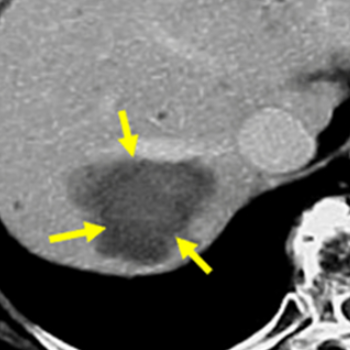

7. 간암의 초기증상 및 증상

간암의 경우 알려진 초기증상은 거의 없지만, 드물게 담관 주위에 암이 생기면 초기 무렵부터 황달이 보일 수 있습니다.

암이 간 내에서 어느 정도 진행하여 커지게 되면, 발열과 복수, 혈관의 팽창 등의 증상이 발생합니다. 또한 담관이 막히면서 황달이 보이는 특징이 있으며, 이런 증상이 나타나면 치료를 하더라도 생존율은 매우 적습니다.